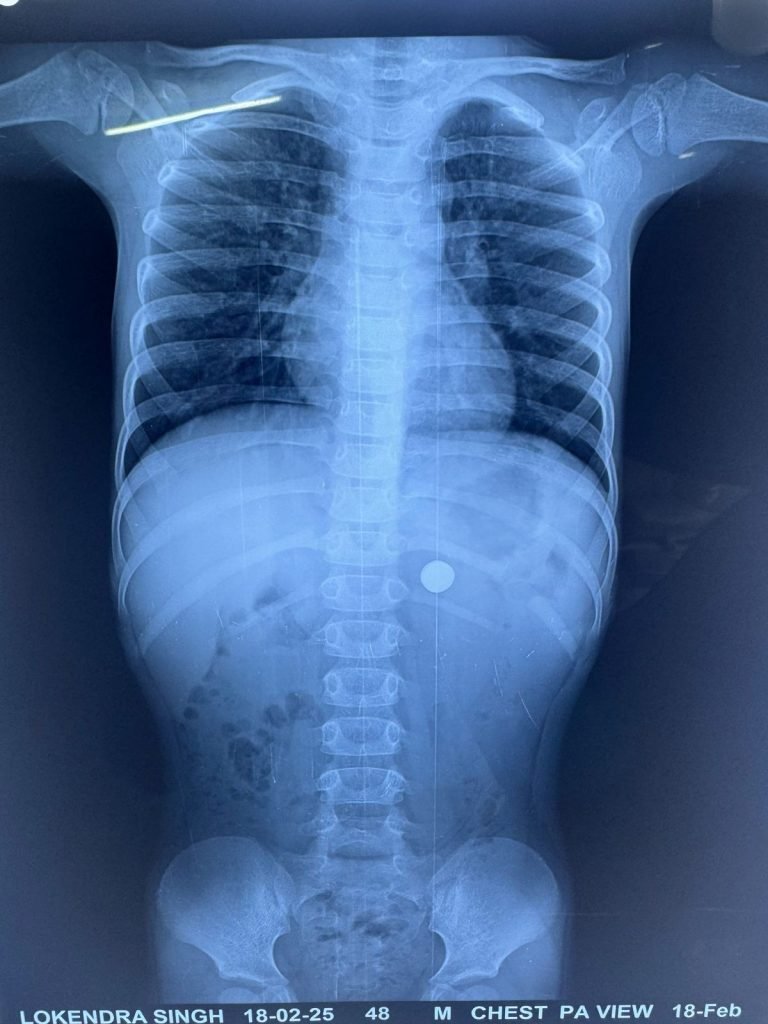

बाल एवं शिशु रोग विशेषज्ञ डॉ.श्याम अग्रवाल ने बताया कि बच्चे के अभिभावको ंने बताया कि दो घंटे पहले बच्चे ने बटन बैटरी निगल ली थी, जिससे उसको हल्का पेट दर्द हो रहा था। बच्चे के पेट का एक्सरे किया गया जिसमें बटन आकृति का बैटरी सैल पाइलोरस (अमास्य व छोटी आंत के बीच की सुकड़े हिस्से) के पास दिखाई दिया। बटन बैटरी की उच्च क्षरणकारी प्रकृति को देखते हुए उसे तुरंत एंडोस्कोपी से हटाने की जरूरत थी।